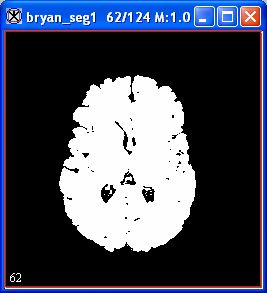

An image appears (Figure 8).

Figure 8. Image produced by using Fuzzy C-Means algorithm